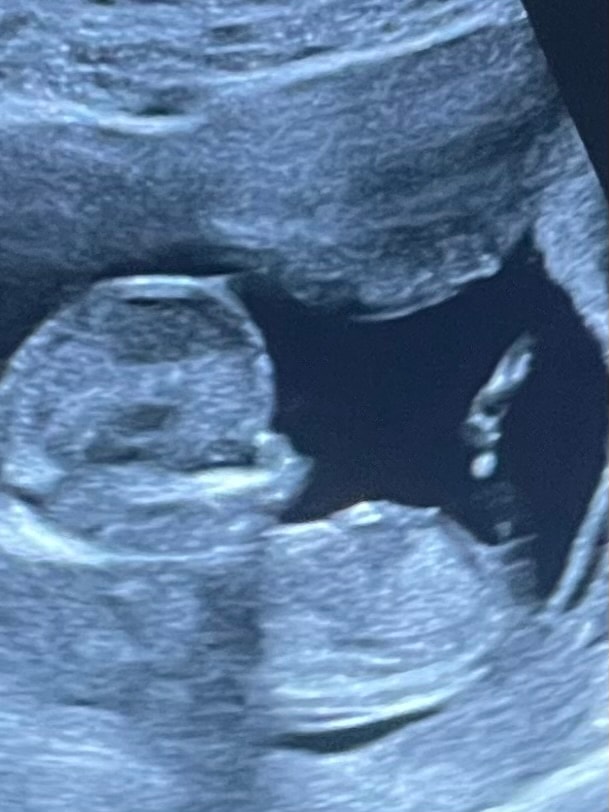

Мальчик или девочка ? Фото узи

На девочку как будто похоже. Если кому-то на 1 скрининге смотрели не по бугорку, а развернув продольно с попы - откликнитесь, подтвердился пол и как там торчит у всех... мне с попы смотрели пол, сказали мальчик, прямо шпулька такая заметная была, но сомнения.

Будем надеяться, что мальчик. Носик для него подходящий 😊

24.04.2022

Думаю, мальчик.

23.04.2022

Мне кажется мальчик

Изображение Мне кажется девочка) у меня есть такое фото, бугорок такой же "лежачий")) но не известно кто, жду 2 скрининг Хочется очень девочку)

По мне, девочка 👧

Похоже на девочку